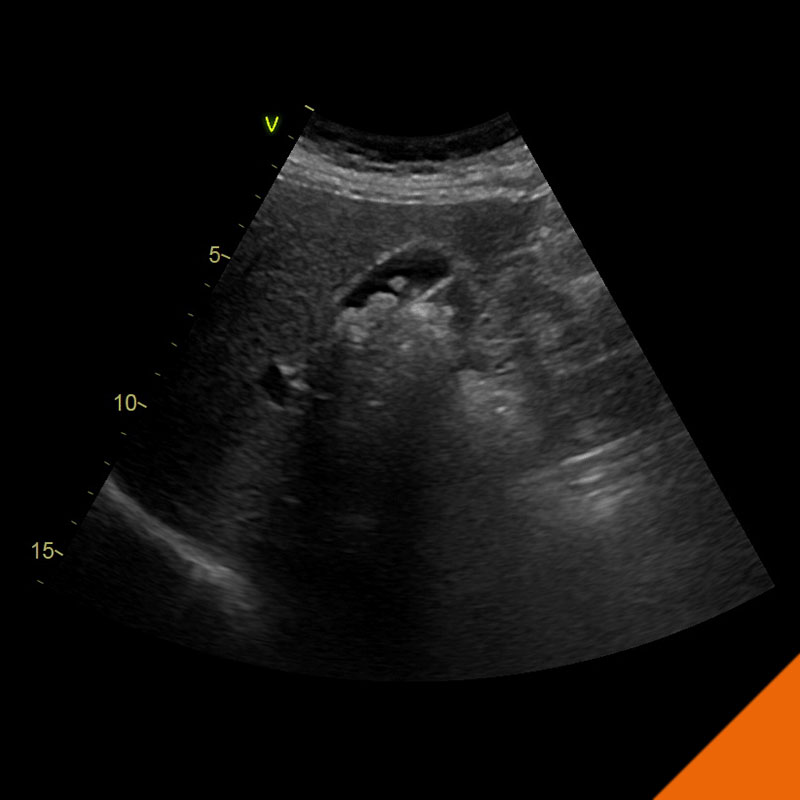

Kardiologie

Seit mehr als 20 Jahren widmen wir uns in unserer Praxis und in der klinischen Forschung der Früherkennung und Behandlung der Herzschwäche.